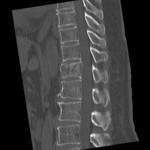

[画像診断]胸椎・腰椎損傷について(外傷)【研修医と学ぶ】 2011-03-29